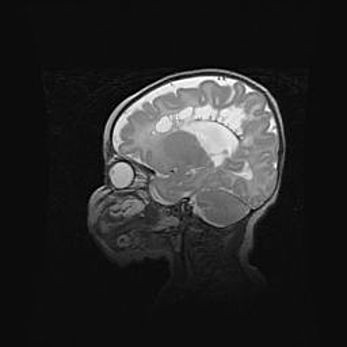

Аномалия Денди-Уокера. Признаки гипоплазии мозолистого тела.

Возраст: 5 месяцев 3 дня

Вес: 5550 г

Пол: мужской

Окружность головы: 39 см

Срок гестации: 40 недель

Аномалия Денди-Уокера – это порок развития головного мозга, для которого характерна триада симптомов: гипотрофия или аплазия червя мозжечка и/или полушарий мозжечка, расширение четвёртого желудочка с формированием ликворной кисты задней черепной ямки, гипертензионная гидроцефалия различной степени.

Гипоплазия мозолистого тела относится к дефектам внутриутробного этапа развития мозговой ткани, возникающим в процессе закладки структур головного мозга, что происходит на начальных этапах развития эмбриона.